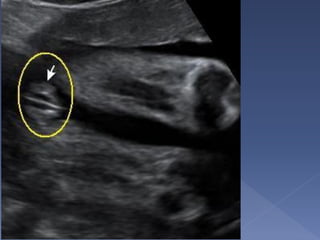

 serves as a monitor for growth of the long

 The femoral shaft is seen as a slightly

curved, echogenic structure that produces

an acoustic shadow